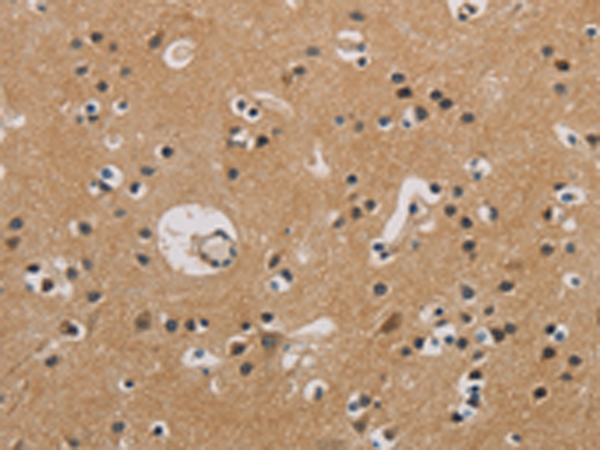

分类: 科研抗体货号: P00470别名:应用: IHC反应种属: Human